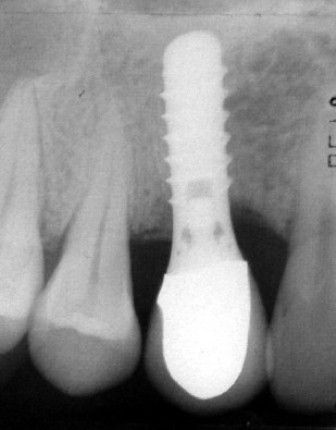

Endosteal implantlar - bu implantlar, cerrahi yöntemle, çene kemiğine direkt olarak implante edilirler. Çevredeki dişeti dokusu iyileştikten sonra, orijinal implanta bağlantı sağlayacak materyali takmak için ikinci bir operasyon gerekir. Son olarak, yapay diş (veya dişler) tek başına veya köprü ya da protez üzerinde grup halinde implanta takılır.

İMPLANTLARIN YERLEŞTİRMESİ VE PROTEZ KADAR SÜRER? Cerrahi işlemin süresi yerleştirilecek implant sayısına ve hastanın koşullarına bağlı olarak yarım saat ile birkaç saat arasında değişebilir. Operasyondan sonra, implant ile kemiğin kaynaşması için (osseointegrasyon) 2-3 ay kadar beklenir. Daha sonra bu implantlar üzerine, birkaç seans süren bir uygulama ile protezler yerleştirilir. İmplantlar dişler çekildikten hemen sonra yerleştirilebilir mi? Evet,günümüzde bu mümkündür.İmplant diş çekimini takiben taze çekim boşluğu içerisine yerleştirilebilir.Buna “immediyat uygulama” denir.